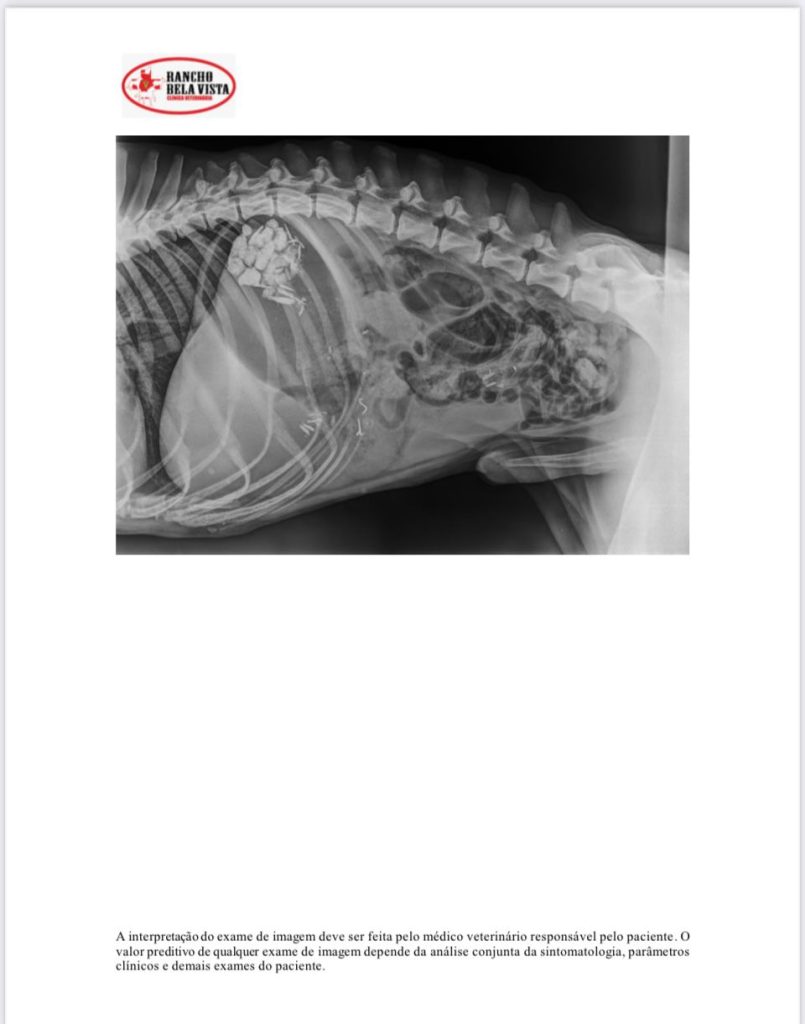

O veterinário Daniel Galante, do Hospital Veterinário, para onde o cão foi levado, disse que as condições eram críticas. Havia pedras e pedaços de ferro no estômago no cachorro.

“Ele estava praticamente em coma, desidratado, passando fome, muito abaixo do peso, com células sanguíneas reduzidas. Não tinha condições de aguentar uma cirurgia. A hipótese é que tenha morrido por causa dessas condições de saúde. Mas pelo que vemos tudo que o cachorro apresentou, era tratável”, explicou o veterinário.

Moradores ficaram com o animal e acionaram a CPI e a prefeitura de Vitória. A equipe de Bem-Estar Animal da prefeitura de Vitória fez o resgate do animal para o hospital veterinário que tem convênio com o município. No local foi constatado que havia pedaços de ferro e pedras no estômago do pit bull. Ele não resistiu aos ferimentos e morreu.